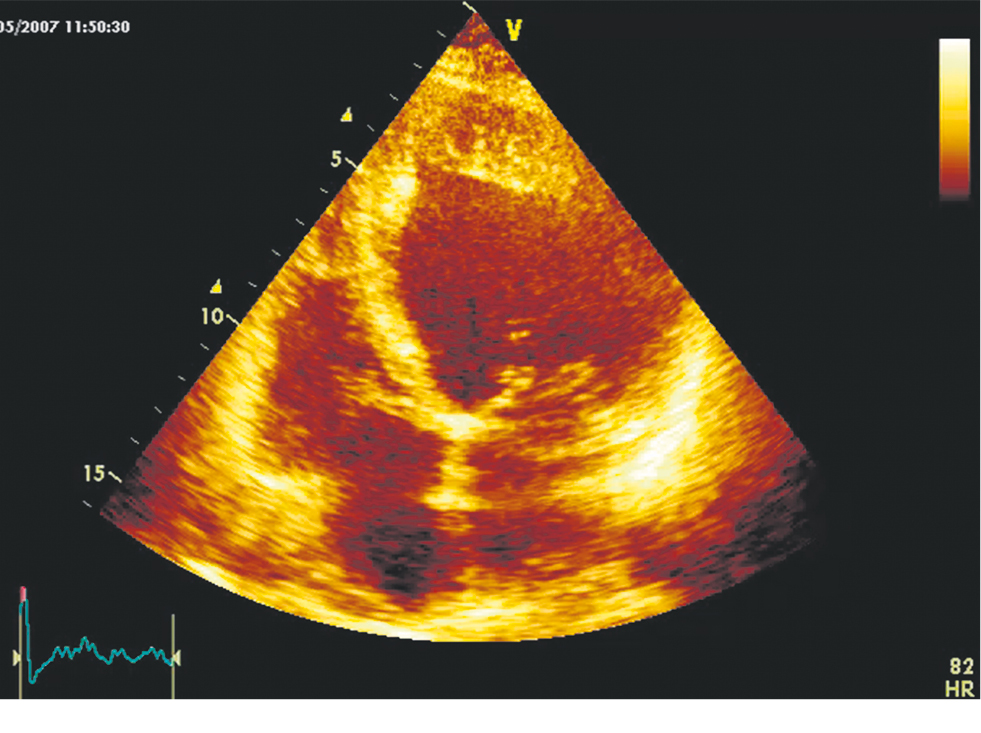

In this article, we use the term LVNC because this is the term used in the 2022 European guidelines for the treatment of ventricular arrhythmias and the prevention of SCD. LVNC includes a heterogeneous group of phenotypically different diseases characterized by specific changes in the LV myocardium and sometimes RV myocardium [2, 78–80]. A structural pathology common to all phenotypes is abnormal trabeculae in the LV/RV or both ventricles, most often in the apical region [78–80]. Figure 5 presents an echocardiogram of one of our patients.

Fig. 5. Echocardiogram of a patient with left ventricular hypertrabeculation. Apical 4-chamber view. Noteworthy is the dilatation of the left ventricle and pronounced trabecularity in the area at the apex

Рис. 5. Эхокардиограмма пациента, имеющего гипертрабекулярность миокарда левого желудочка. Верхушечная 4-камерная позиция. Обращают на себя внимание дилатация левого желудочка и выраженная трабекулярность в области верхушки